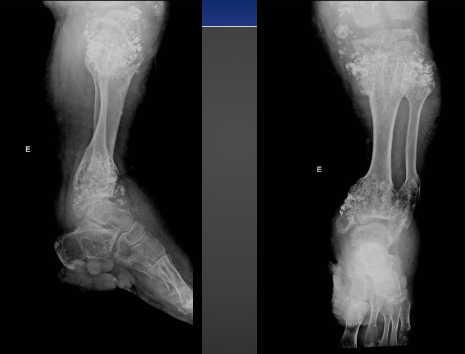

Enchondromatosis

-AKA Ollier’s disease

-Uncommon

-Multiple enchondromas that can be very large and cause severe deformity

-Chance of malignant transformation 10-50%

Enchondromatosis on X-ray

Enchondromatosis on X-ray (not in hands)

Maffucci Syndrome

-Rare

-Multiple enchondromas with soft tissue hemangiomas

-Malignant transformation in 25 to 50%

Maffucci Syndrome on X-ray